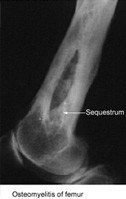

Ostemyestis